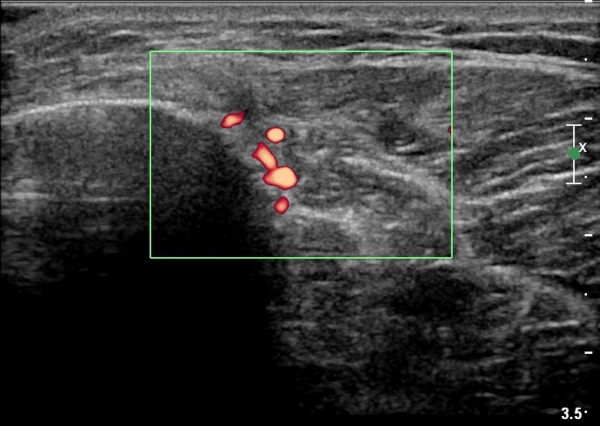

[¹«¸­] °æ°ñ ÇǷΰñÀý ÃÊÀ½ÆÄ¼Ò°ß(sonographic findings of stress fracture of tibia)

¿ìÃø ¹ß¸ñ°ú ¾Æ·§´Ù¸® ÅëÁõ(±â°£ 2ÁÖ)

±º´ë¿¡ ÀÔ´ëÇÏ¿© ÈÆ·ÃÀ» ¹ÞÀº º´·ÂÀÌ Àִ ȯÀÚ´Â ¾à 2ÁÖ ÀüºÎÅÍ ¹ß¸ñ ºÎÀ§ÀÇ ÅëÁõÀÌ ÀÖ´ø Áß

ÃÖ±Ù¿¡´Â ¹ß¸ñ À§ ¾Æ·§´Ù¸®¿¡ ÅëÁõÀÌ ¹ß»ýÇÏ°í ½ÉÇÏ°Ô °ÉÀ¸¸é ½ÉÇØÁö´Â ¾ç»óÀÓ

¾Æ·§´Ù¸® Áß°£ ºÎÀ§¿¡ °æ¹ÌÇÑ ¿¬ºÎÁ¶Á÷ ºÎÁ¾ÀÌ °üÂûµÇ°í ¾à°£ÀÇ ±¹¼ÒÀû ¾ÐÅëÀ» º¸ÀÓ.

ÃÊÀ½ÆÄ °Ë»ç

¹Ì¼¼ÇÏ°Ô ¿¬ºÎÁ¶Á÷ ºÎÁ¾°ú °¡°ñ Çü¼ºÀÌ °üÂûµÊ.

Bilateral stress fracture of the tibia diagnosed by ultrasound. A case report

https://www.ncbi.nlm.nih.gov/pmc/articles/PMC3558228/pdf/main.pdf